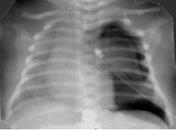

Выраженное снижение пневматизации легких, воздушные бронхограммы, границы сердца практически не различимы, стёрты (Рис.6).

Рисунок 6.

РДС. Рентгенограмма грудной клетки в прямой проекции, в горизонтальном положении. Интенсивное мелкоточечное затемнение легочных полей - с-м "матового стекла", на фоне которого не дифференцируется тень средостения. Визуализируются линейные просветления, обусловленные заполненными воздухом бронхами - "воздушная бронхограмма". (

Диагностика и лечение РДС недоношенных // метод. рекомендация, 2007)